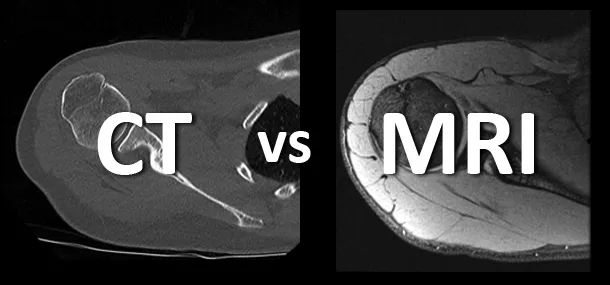

除了PET/CT,还出现了 PET/MRI 等应用。但无论哪种融合,这些融合机型的本质仍为PET, CT和MRI仅是为了弥补PET解剖的不足,使其功能更加完美。